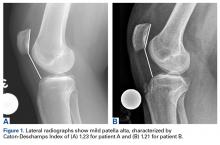

The PTI is correlated with tibia-based measures of height, but the correlation is not perfect. Lower degrees of overlap between the patella and the trochlea (PTI <0.15) and significant functional patella alta may warrant adding TTDO in cases of borderline CDI (1.2-1.4). Figures 1A, 1B and 2A, 2B show the imaging of 2 patients with relatively similar patellar height (assessed with CDI) but quite different degrees of overlap between the patella and trochlea. The patient with less overlap is more likely to have delayed patellar engagement and symptomatic patella alta and thus may be a poorer candidate for isolated MPFL reconstruction. For additional information, please refer to the work by Roland Biedert, MD, who has proposed trochlear lengthening in these situations.13Physical examination (even in the era of advance imaging) continues to provide useful insight into whether to add TTDO. One physical examination test that can help in understanding patellar-